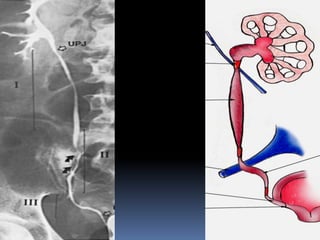

 Radiological

 IVU: Stone appear as filling defect , obstruction & Back pressure Not useful if the

Investigations

Right Upper Ureteric StoneKUB IVP